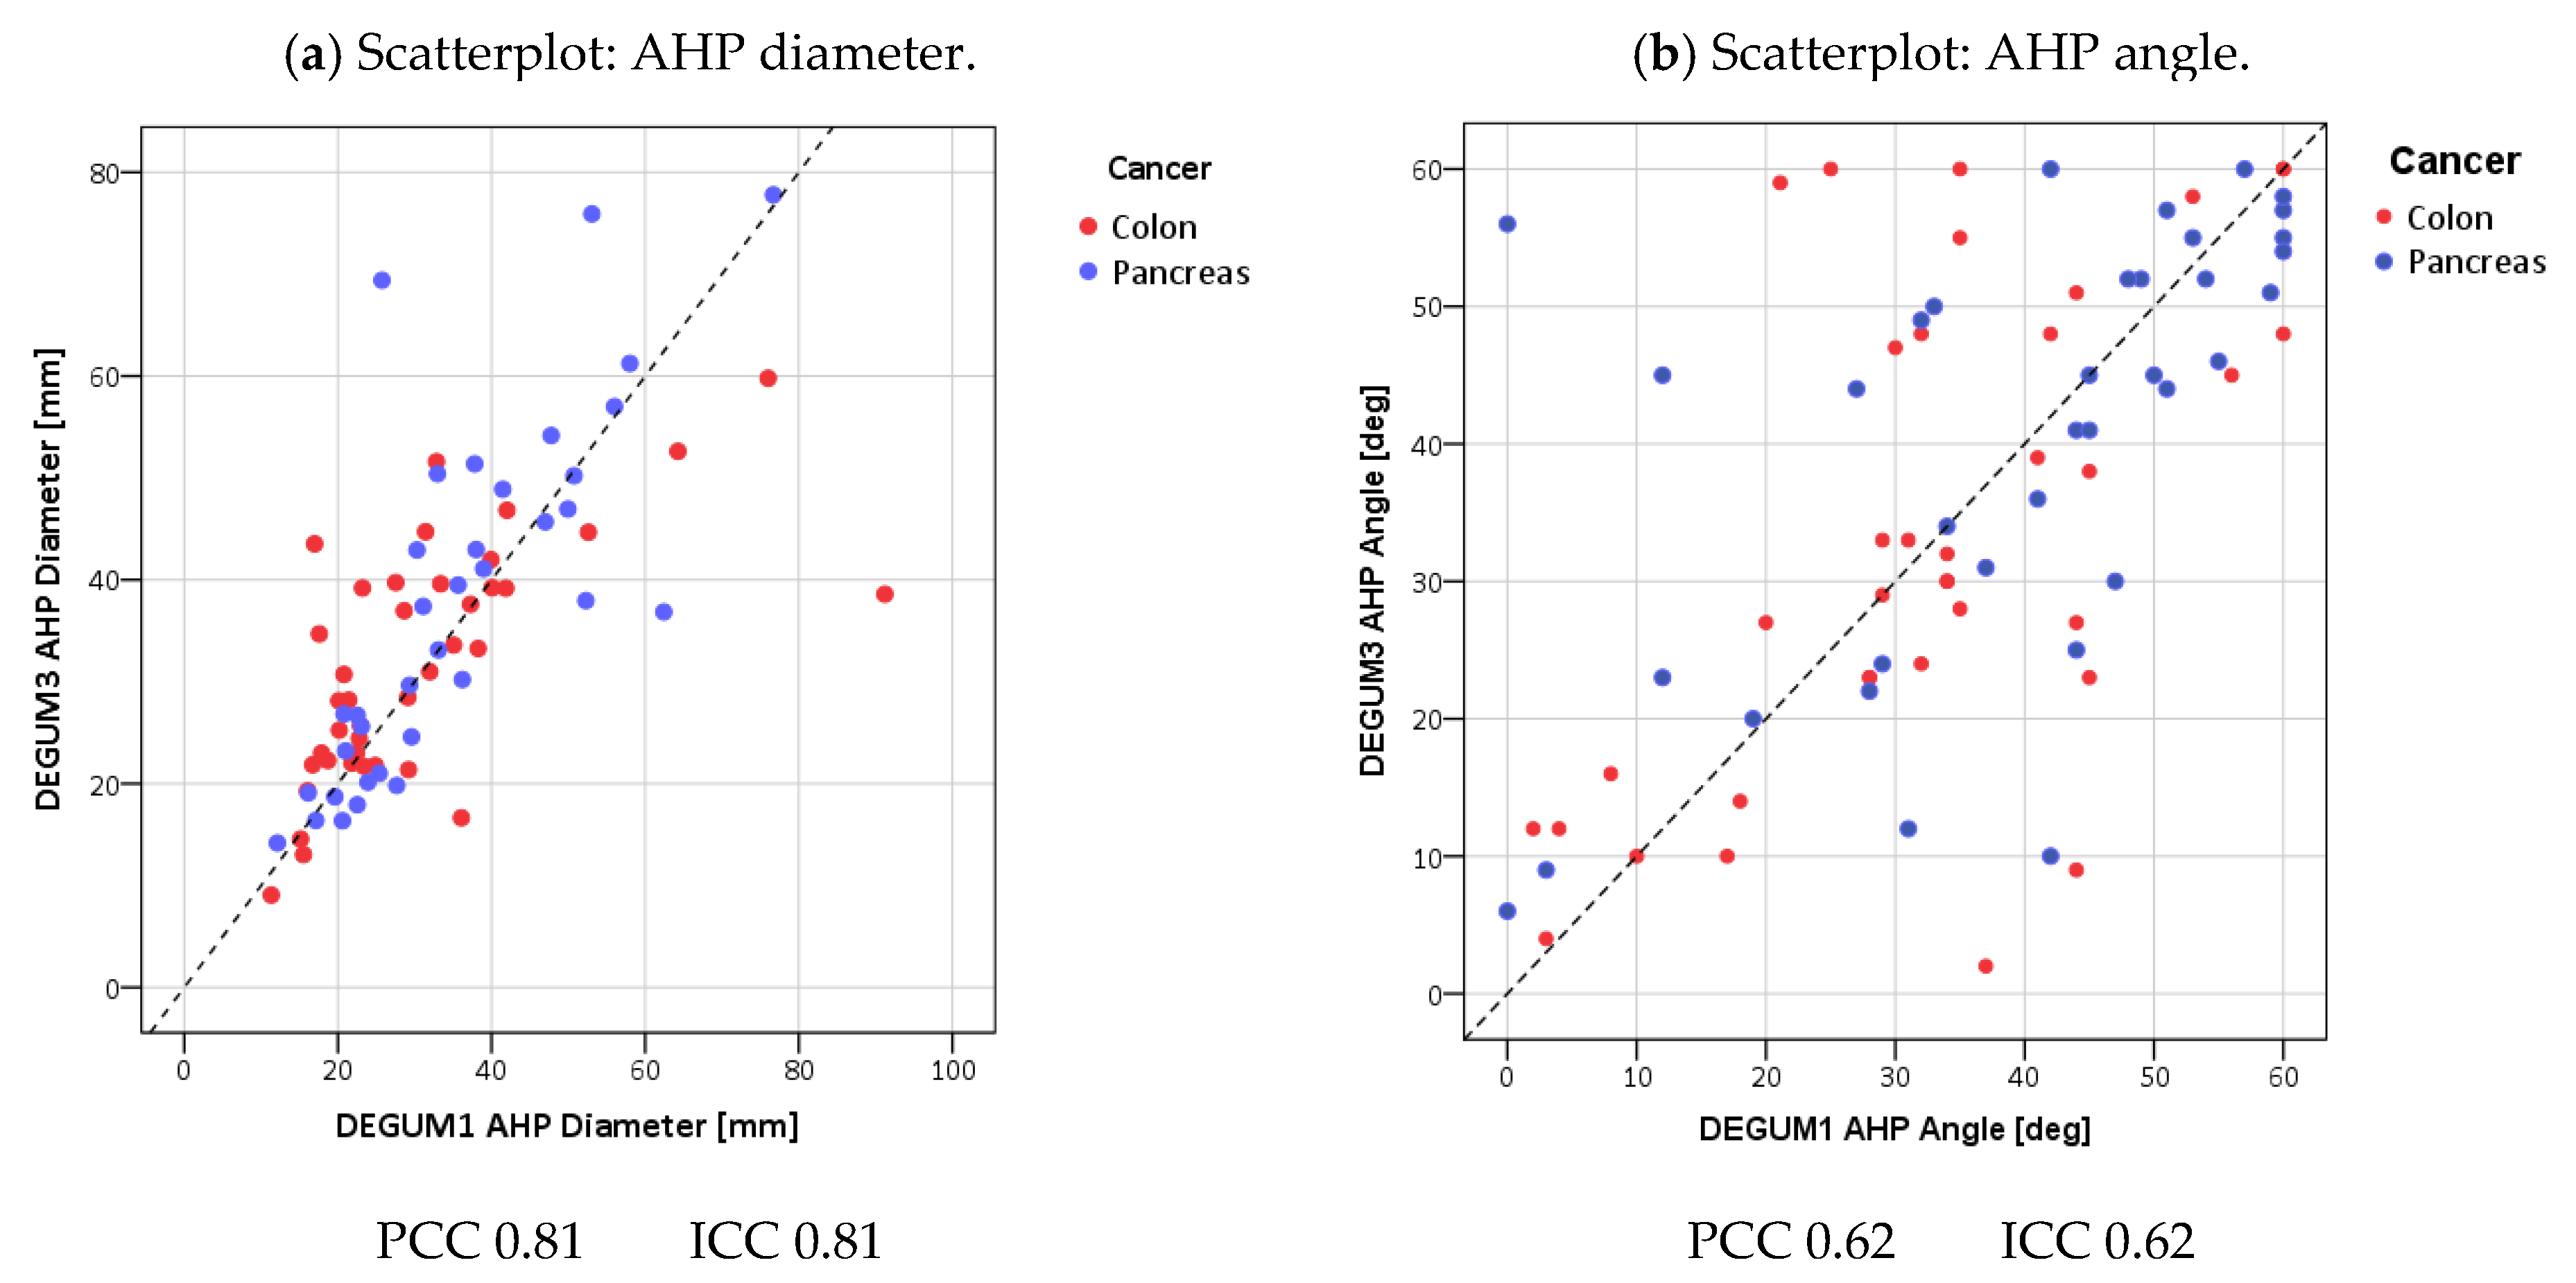

| Parameter | Diameter [mm] | Insonation Angle | Doppler Shift [cm/s] | Flow [mL/min] | AHP-DPI |

|---|---|---|---|---|---|

| N | 79 | 76 | 76 | 76 | 76 |

| Mean D1 (SD) | 4.4 (0.7) | 35.8 (16.9) | 24.6 (11.3) | 308 (165) | 0.3 (0.1) |

| Mean D3 (SD) | 4.5 (0.7) | 36.6 (17.3) | 25 (9.4) | 332 (166) | 0.3 (0.1) |

| Mean tot (SD) | 4.5 (0.7) | 36.2 (17) | 24.8 (10.3) | 320 (165) | 0.3 (0.1) |

| Mean Diff (SD) | 0.1 (0.4) | 0.8 (14.9) | 0.5 (8.5) | 24 (86) | 0.01 (0.05) |

| p(Bias) | 0.10 | 0.98 | 0.14 | 0.05 | 0.06 |

| p(Var) | 0.38 | 0.33 | 0.25 | 0.94 | 0.66 |

| PCC | 0.81 | 0.62 | 0.68 | 0.87 | 0.90 |

| ICC (95% CI) | 0.81 (0.71; 0.87) | 0.62 (0.46; 0.74) | 0.67 (0.52; 0.78) | 0.86 (0.78; 0.91) | 0.90 (0.84; 0.93) |

| MVC | 0.05 | 0.27 | 0.15 | 0.13 | 0.08 |

| B/A Limits | (−0.79; 0.94) | (−28.5; 30.1) | (−16.1; 17.0) | (−145; 192) | (−0.09; 0.11) |